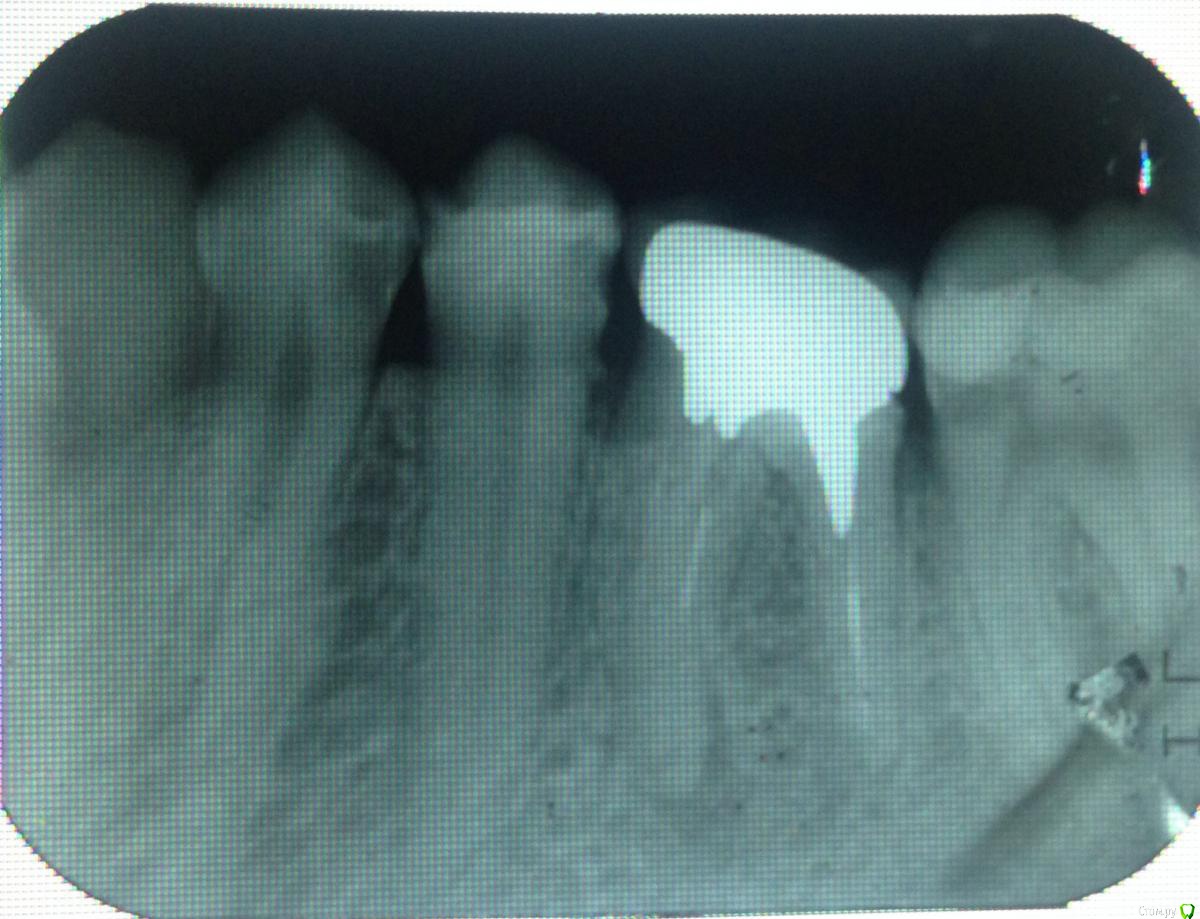

Даночка Опубликовано 5 мая, 2015 Поделиться Опубликовано 5 мая, 2015 (изменено) Здравствуйте. Есть ли в 45 зубе кариес, так как он остро реагирует на холодное?Делала снимок, чтобы спросить за 45-й зуб, но увидела в 46-м не запломбированные каналы, и, как мне кажется ,периодонтит. Так ли это? Коронку в 46-м ставили около года назад. Изменено 6 мая, 2015 пользователем Даночка Ссылка на комментарий

Чертков Александр Опубликовано 6 мая, 2015 Поделиться Опубликовано 6 мая, 2015 Здравствуйте. Кариес в 4.5 есть ( а возможно и пульпит ). Зуб 4.6 надо "переделывать" полностью (снимать коронку, извлекать штифтовкладку, перелечивать корневые каналы, и заново восстанавливать: штифтовкладка + коронка). Также детально оценить зуб 4.7 (есть подозрение - по рентгену - что под пломбой рецидив кариеса) 3 Ссылка на комментарий

molchanoff Опубликовано 6 мая, 2015 Поделиться Опубликовано 6 мая, 2015 44 похоже тоже с кариесом 1 Ссылка на комментарий